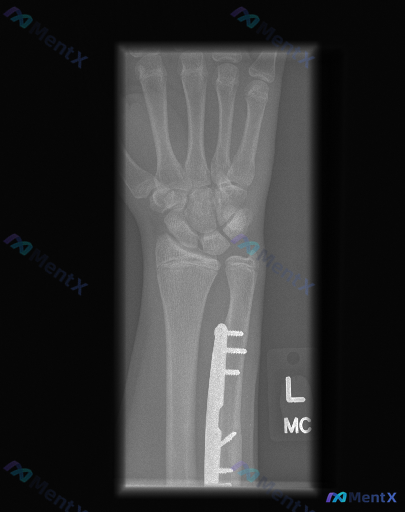

整理到一张青少年左侧前臂及手腕的正位X光片,背景是左尺骨远端骨折术后复查。

- 尺骨远端可见钢板+螺钉内固定,位置尚可,螺钉无明显松动/断裂;固定区域骨折线模糊,有连续骨痂通过。

- 桡骨远端骨皮质完整,未见明显新鲜骨折线。

- 下尺桡关节间隙看起来有增宽,尺骨远端相对于桡骨的位置好像不太对。

- 尺桡骨远端骨骺线清晰可见,未闭合。

- 腕关节周围软组织有轻度肿胀,没有明显异物或积气。